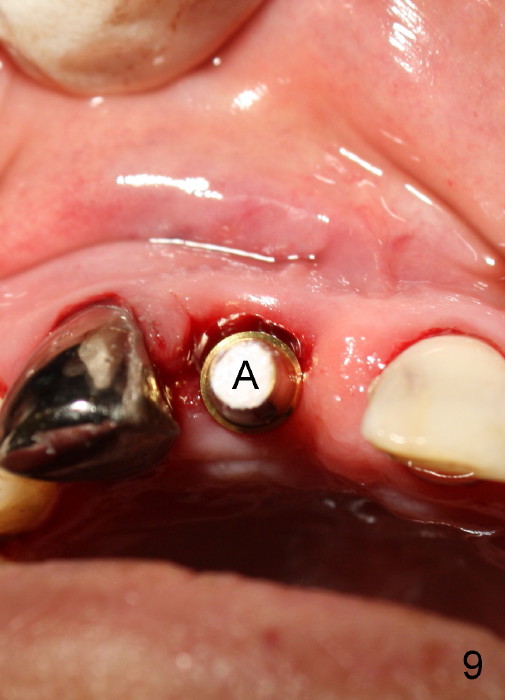

A 64-year-old lady requests replacing #7 and 8 crowns (Fig.1,2). When #8 is extracted, the labial plate is found to be missing (Fig.3). Following 2 mm pilot drill (Fig.4,5 P), 3.8 mm tap drill (Fig.6,7 T) and 4.5x14 mm implant (Fig.8 I) and 4.8 mm abutment (Fig.9 A), corticocancellous bone is harvested from the left tuberosity and placed in the labial gap of the socket (Fig.10 G). Collagen dressing is placed over the bone graft (Fig.11 C). The former is secured in place by an immediate provisional (P).